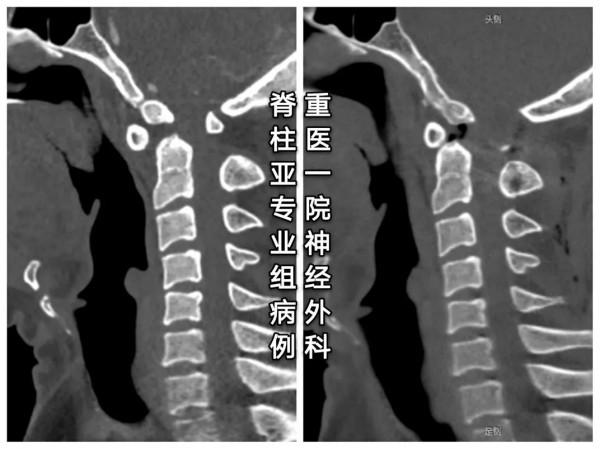

診斷:齒狀突小骨

還是來看看椎動脈高跨

似乎完全不能置釘?

- 大多數看似不可能置釘的有椎動脈高跨的C2椎弓根,其實都是可以置釘的

- 面對椎動脈高跨,“小心假設,大膽求證”,總能找到合適的釘道。

- 本例選擇靠近C1-2小關節的上關節面和靠近C2峽部內側的位置建立釘道。